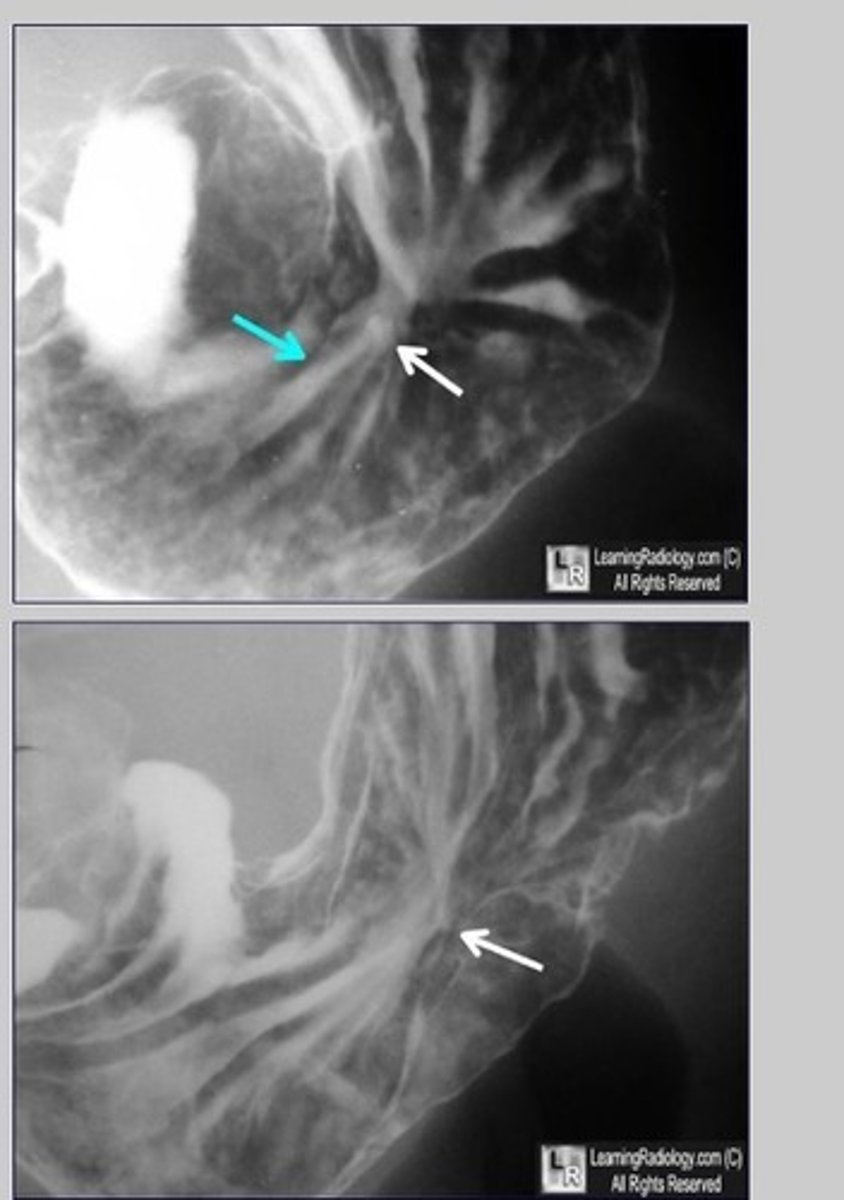

ulcer

Ulcer (pic 2)